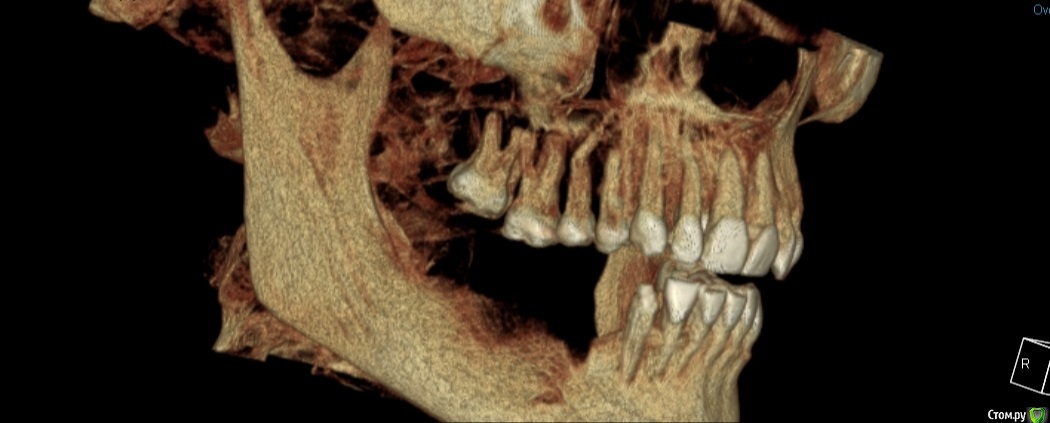

Екатерина Ч. Опубликовано 10 октября, 2020 Поделиться Опубликовано 10 октября, 2020 Здравствуйте. У меня при широком открытии рта в хрустит в челюсти. Что это может быть? Планирую делать имплантацию зубов на нижней челюсти не будет ли из-за этого проблем. У ортодонта не была. А имплантолог ничего не сказал. Ссылка на комментарий